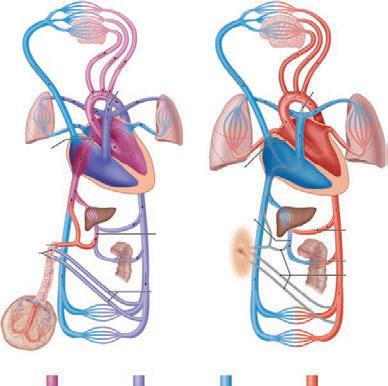

Obr. 1.1 Schéma oběhu: a) intrauterinně; b) extrauterinně [1]

hlava, krk, horní končetiny

pravé plicní křídlo

ductus

arteriosus Botalli foramen ovale levé plicní křídlo

pupeční žíla (v. umbilicalis)

pupeční arterie (aa. umbilicales)

pupečník a

střevo játra

dolní končetiny

portální žíla (v. portae)

iliacké arterie (aa. iliacae)

obliterovaný ductus Botalli

levé plicní křídlo

uzavřené foramen ovale

portální žíla (v. portae) b

arteriální smíšená krev venózní smíšená krev